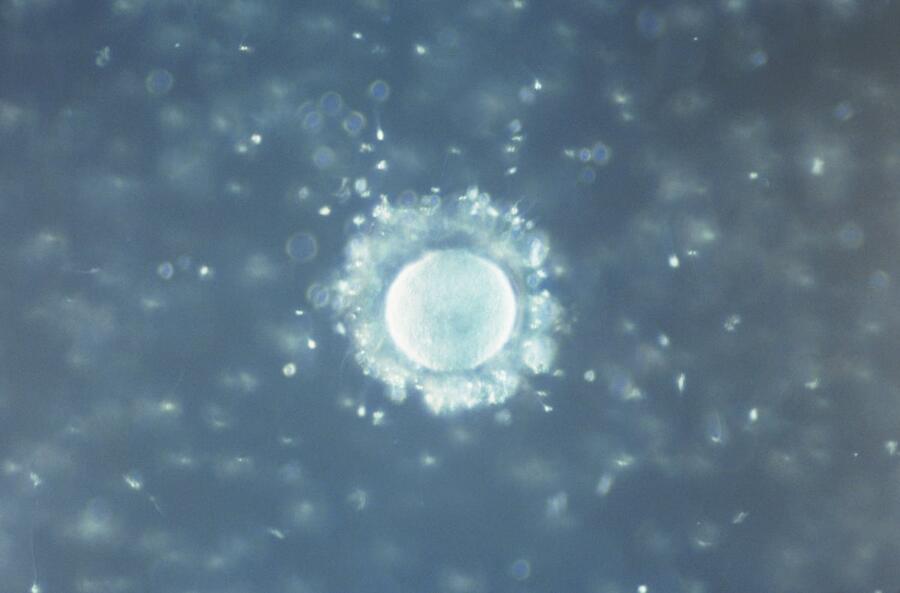

Spanish researchers have identified different types of plastics in seminal plasma and ovarian follicular fluid >>>